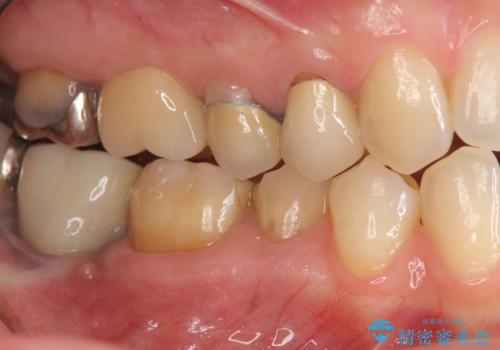

- 歯にものがつまり、以前治療したクラウンの見栄えの悪さの改善を求めて来院されました。

歯ぐきとの境目が、クラウンでしっかりと覆われていないため精密なセラミッククラウンで機能性を回復していきます。

- 40万円(仮歯・ファイバーコア・ジルコニアクラウン×3)費用は治療当時の料金となります